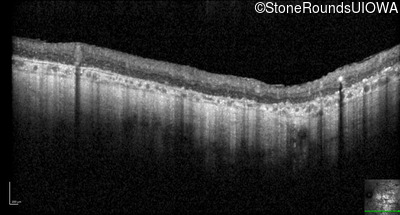

Optical Coherence Tomography - Right - Hand Motion sc

Exemplar / OCT Stack